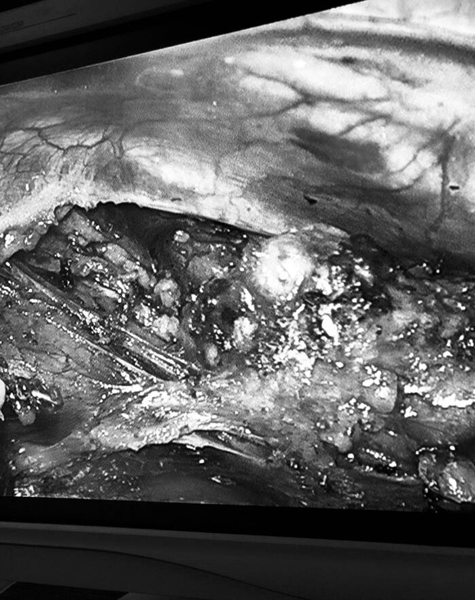

患者转入心胸外科后,身体状况表现极差,有营养不良、全身无力、吞咽困难等情况。主任何帆查房后,考虑患者为胸腺瘤合并重症肌无力IIB型,立即给予溴比斯的明对症治疗,治疗后肌无力症状好转。随即,何帆主任组织全科讨论患者病情,设计手术方案,最终于8月16日由马明生、尹皓原医生为患者实施根治术。手术采用单孔经右侧腋前线第三肋间进去胸腔,外科医师通过传输到监视器中的图像,引导操作外科手术器械实施手术,切口长约3厘米,真正实现微创手术治疗。在胸腔中实施时,称为胸腔镜手术,具有手术创伤小、术后疼痛轻、并发症少、恢复快等优点。

术中发现肿瘤有3厘米*4厘米,与心脏大血管,前胸壁以及对侧胸膜粘连较紧,手术难度大,稍有不慎可能导致心脏大血管破裂导致大出血。经过2个小时的手术,患者肿瘤病灶被清除。术后患者顺利康复出院

术前

术后